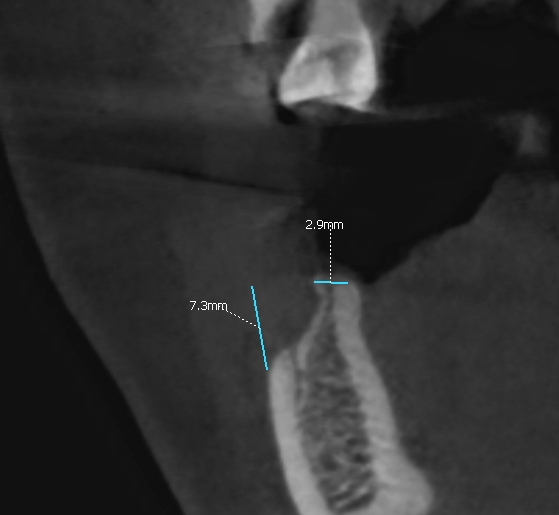

Ryc. 2. Szerokość wyrostka. Ryc.  3. Deficyt objętościowy masy kostnej i zanik blaszki przedsionkowe.

Po okresie 6 miesięcy wykazano prawidłową resorpcję cementu i regenerację wyrostka poprzez odtworzenie kości żywiciela (pacjenta) do szerokości około 8 mm (ryc.13).

Regenerację blaszki przedsionkowej potwierdzono także klinicznie po odwarstwieniu płata podczas zabiegu planowej implantacji. Zmierzono szerokość wyrostka na poziomie 7-8 mm (ryc.14). Po wyrównaniu płaszczyzny wyrostka (ryc. 15) wykonano łoża dla implantów śrubowych w okolicy 45 (dł. 10 mm, śr. 3.7 mm) i 46/47 (dł. 10 mm, śr. 4.1 mm) (ryc.16), które wprowadzono w kość z momentem obrotowym około 25 Ncm. Ranę zaopatrzono szwami (PTFE – politetrafluoroetylen 4-0, igła odwrotnie tnąca, profil 3/8 koła długość 16 mm) (ryc.17).